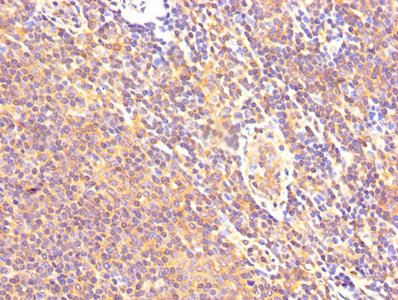

IHC image of CSB-PA004561YA01HU diluted at 1:500 and staining in paraffin-embedded human lymph node tissue performed on a Leica BondTM system. After dewaxing and hydration, antigen retrieval was mediated by high pressure in a citrate buffer (pH 6.0). Section was blocked with 10% normal goat serum 30min at RT. Then primary antibody (1% BSA) was incubated at 4°C overnight. The primary is detected by a biotinylated secondary antibody and visualized using an HRP conjugated SP system.